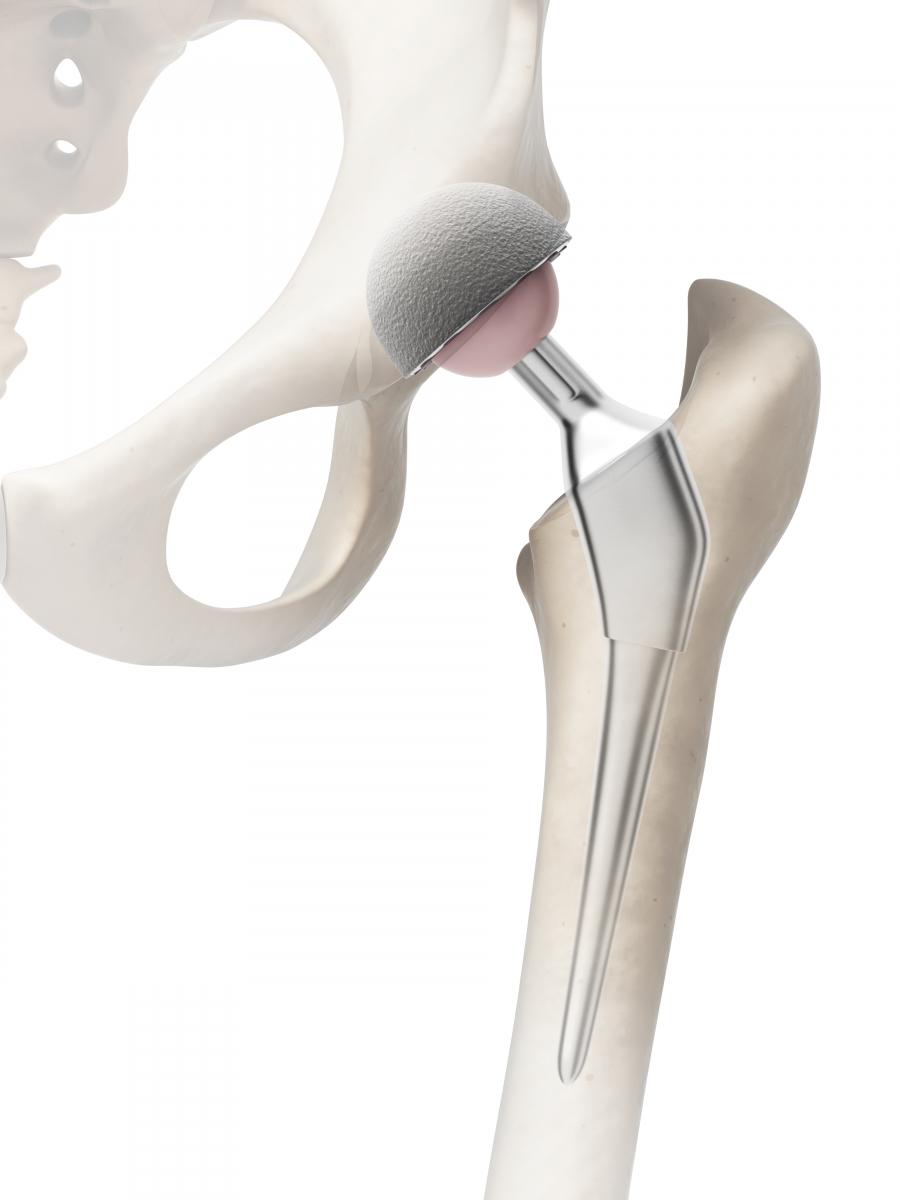

Эндопротезирование тазобедренного сустава: фото и схемы